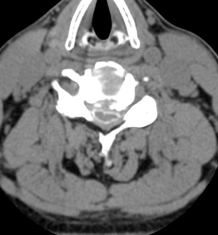

术前脊髓造影后CT,明显可见脊髓压迫